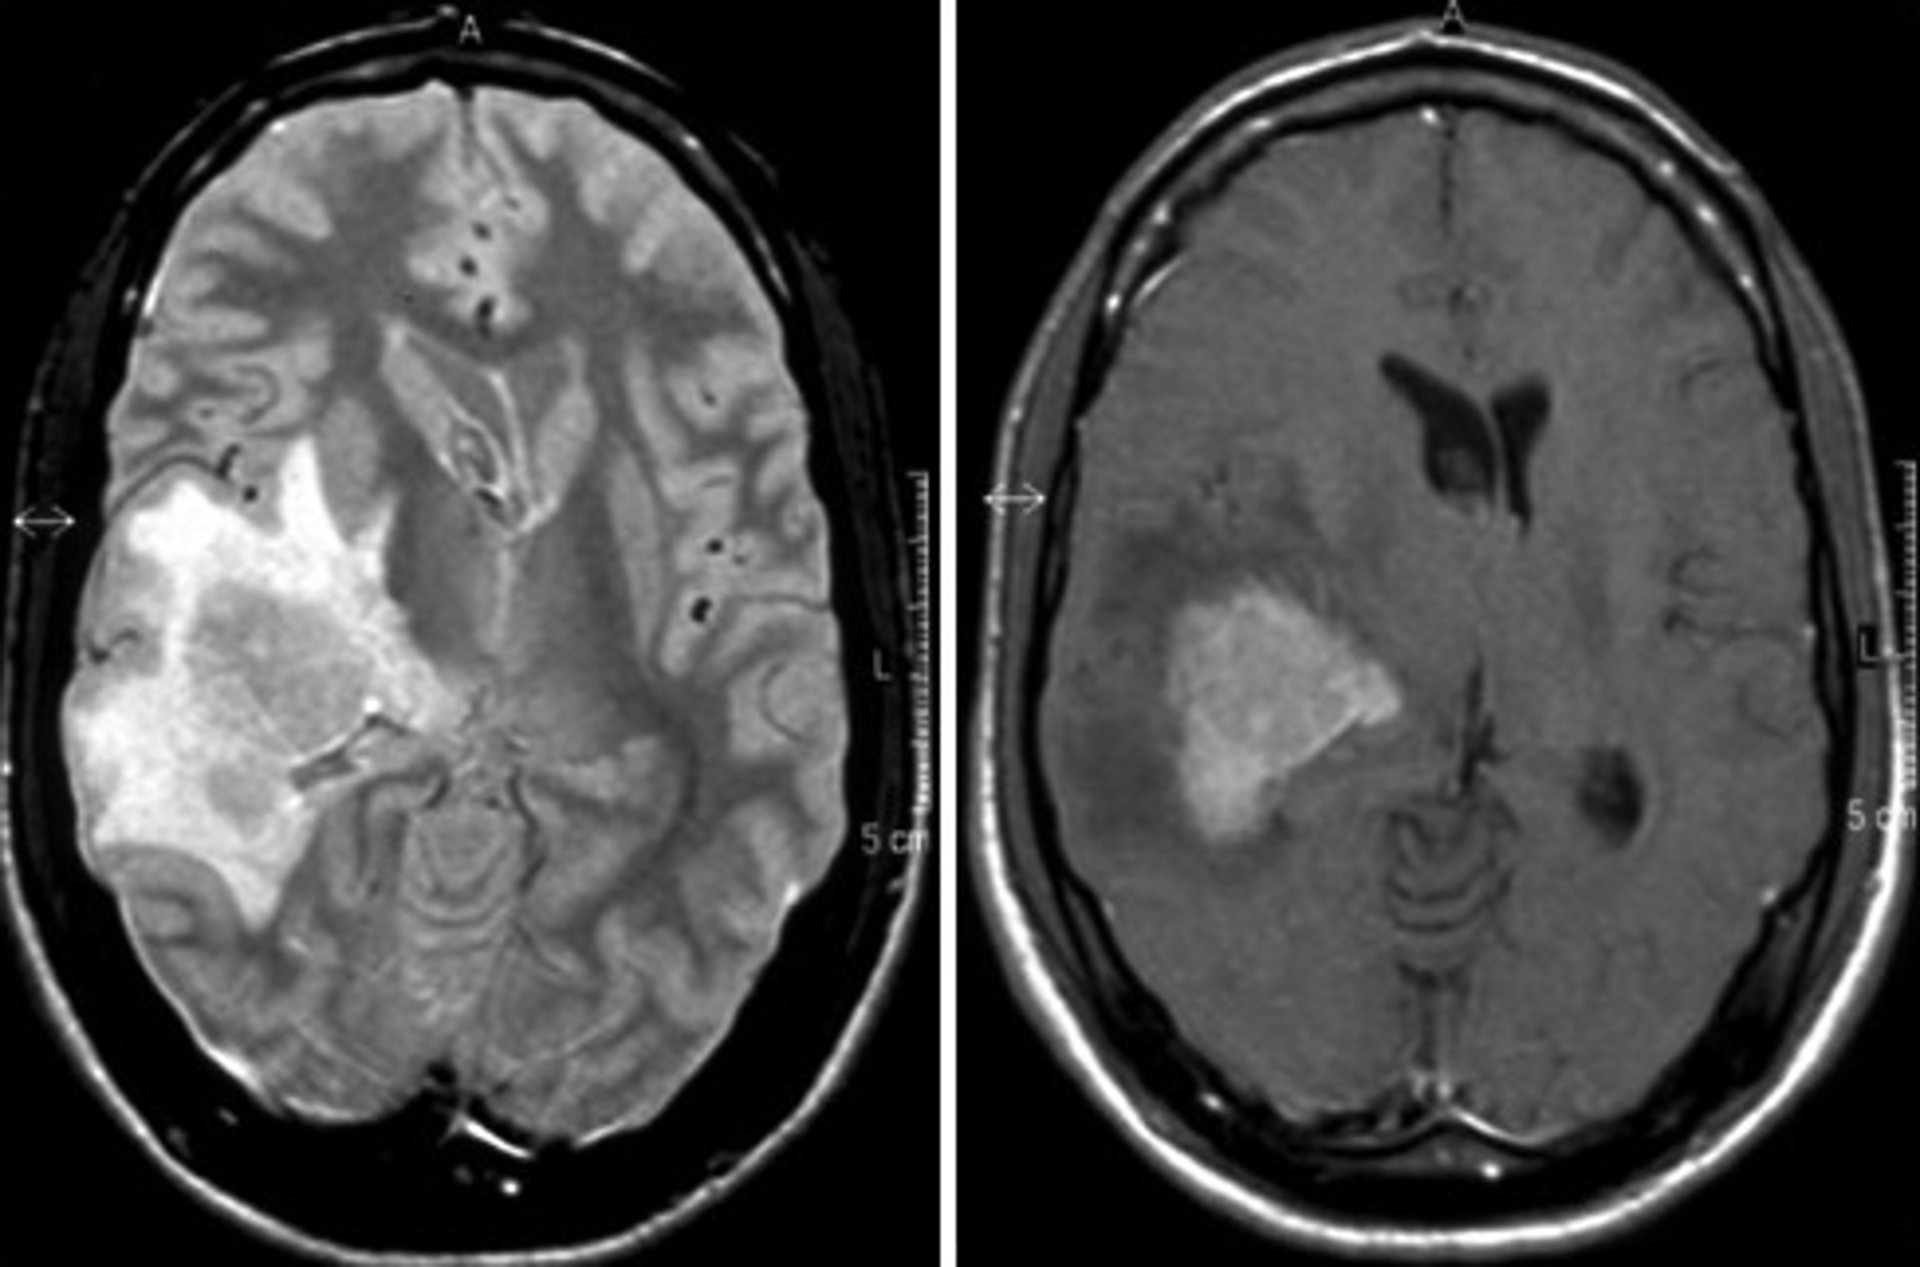

Linfoma cerebral

Linfoma cerebral - HOSPITAL RUBER INTERNACIONAL

Ahora bien, los hematólogos de este hospital aseguran que el linfoma cerebral se trata de un tumor "raro" debido a su baja incidencia, de modo que "puede resultar difícil la realización de un diagnóstico temprano". Por este motivo, en cuanto aparecen los primeros signos y síntomas, los especialistas realizan pruebas de imagen cerebral, como un escáner y una resonancia magnética.

Además, según explica el doctor Cornago, si se descarta un accidente cerebrovascular y aparece una masa cerebral, "se biopsia dicha lesión. Así, con el resultado histológico, se podrá llegar con certeza al diagnóstico de linfoma cerebral". En ese sentido, destaca que la biopsia es la manera de confirmar que se trata de esa enfermedad y no de otros tumores cerebrales primarios u otras entidades como infecciones.